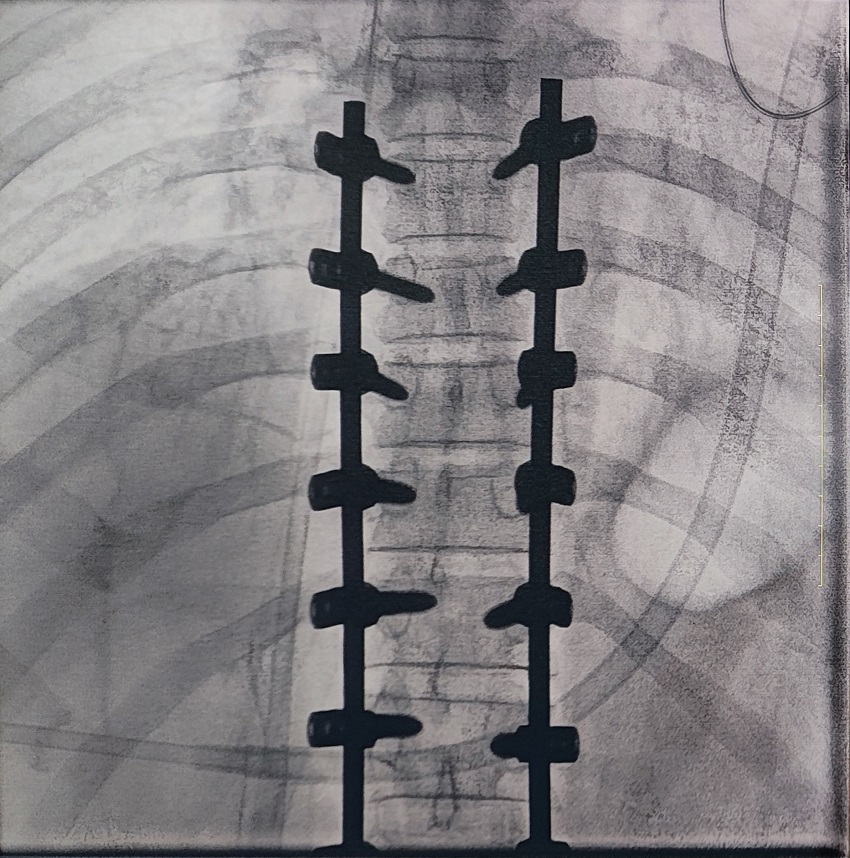

一场脊柱手术中,医生需要拍摄跨越7个节段的脊柱影像,由于曝光的视野较大,常规视野的C形臂通常需要拍摄2-3次,普爱医疗大平板一体式C形臂30CM*30CM的“大视野”,辅助医生一次性完成了7个节段的拍摄。最终,医生在高清影像的辅助下完成了14枚螺钉的精准定位、置入。

大视野,不仅意味着医生可以更快,获取更全面的影像信息,做出精准判断,无需多次拍摄定位,也显著地降低了患者接受的辐射剂量,保护了患者的安全。